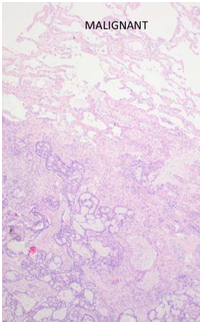

neoplastic tissue benign vs malignant

malignant tumour